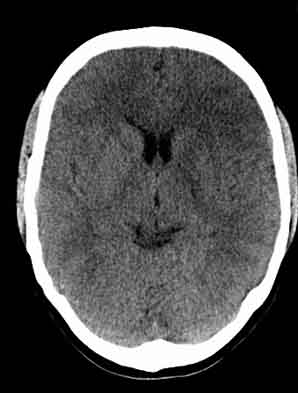

患者,女,29,头痛呕吐2月余,已建议增强或mri进检。

额叶低密度影,建议增强。

左额叶白质密度减低,考虑脑炎,建议增强或mri .

左侧额叶见低密度影,边界模湖 建议 增强 除外占位

左额叶低密度灶考虑炎性病变

双侧脑室前角、旁周围白质低密度减低,边界模糊不清,患者女性:大胆推测,脑白质脱髓鞘改变。mri检查

左侧额叶见低密度影,边界模湖,考虑脑炎, 建议增强除外占位.

左额叶低密度灶,建议mri扫描或增强!